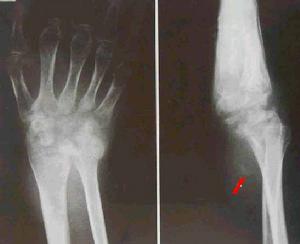

3)肺外器官結核病:或稱肺外結核病,大多是原發性肺結核病經血道播散的後果。在原發綜合徵期間如有少量結核桿菌經原發灶內的毛細血管侵入血流,則能在肺外某些器官(骨關節,泌尿生殖器官、神經系統、漿膜、皮膚等)內形成個別的結核病灶。這些病灶可自愈或潛伏下來,經過較長時間後,當機體抵抗力下降時乃惡化進展為肺外器官結核病。

四、繼發肺外結核:機體抵抗力低時肺病灶中結核菌可經淋巴、血行播散至全身;常並發的肺外結核有腦膜、泌尿生殖道、骨關節結核,以及腹盆腔結核,淋巴結核。